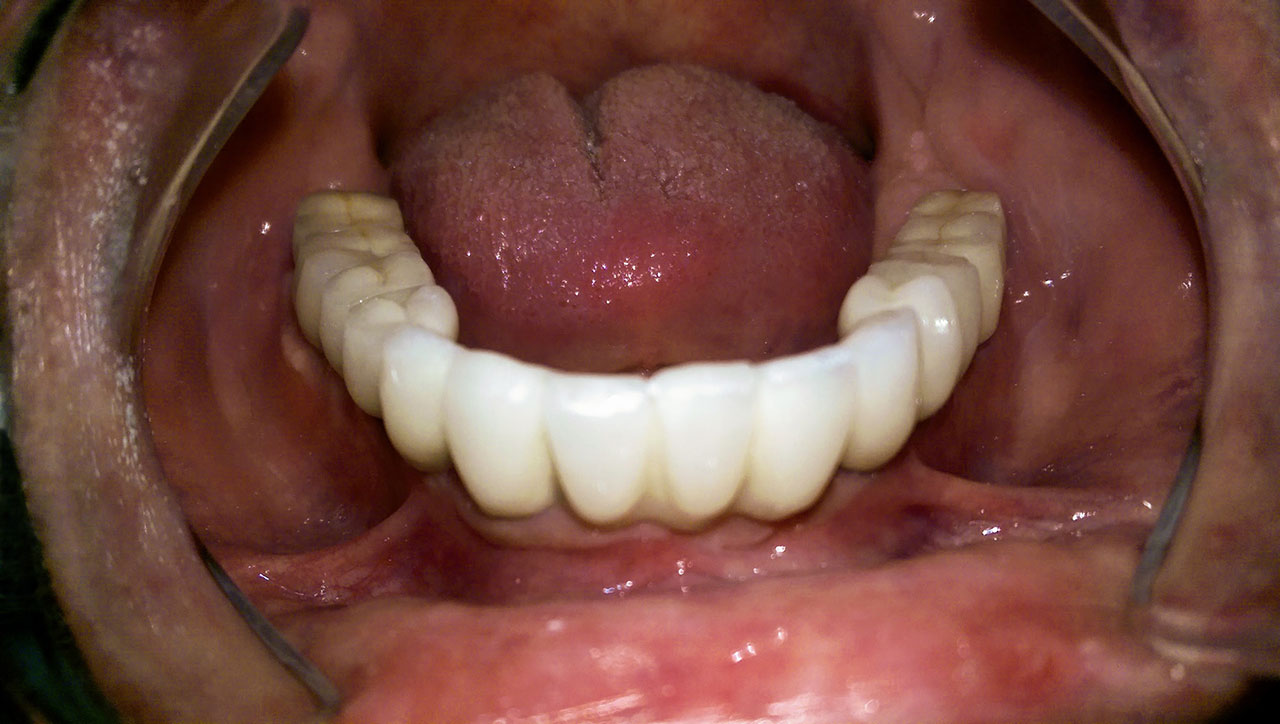

Elhanyagolt fogsor cseréje 2 nap alatt

2 nap alatt varázsoltuk ezt a szép esztétikus alsó, felső körhídat implantátumokkal megtámasztva a korábban elhanyagolt szájba. Az 1. nap 26 fogat távolítottunk el, mert annyira rossz állapotban voltak, és rögtön azonnal terhelhető IHDE svájci implantátumokat raktunk be, fentre 8, lentre 6 darabot. A sebeket összevarrtuk és intraorális szkennerrel digitális lenyomatot vettünk. 2 nap múlva pedig beragasztottuk a kész PMMA műanyag körhidakat. Dr. Kelemen Péter és a Symbion Fogtechnika munkája.